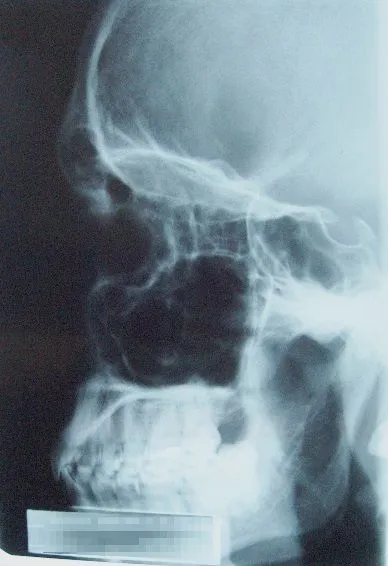

After a car accident or other facial trauma, you may require surgery to correct the damage. Oral and Maxillofacial surgeons are specially trained to perform all types of surgery that is needed after facial trauma. Facial trauma can be repaired in a local hospital or outpatient surgery center. Some of the types of facial trauma, which may require surgery, include facial lacerations, knocked out teeth, broken or fractures cheek, nose, jaw, or eye socket.

Facial trauma causes a high degree of physical and emotional trauma to the patient. Correcting facial trauma requires special training and an in depth understanding of the long term functioning and appearance of the face. Oral and Maxillofacial surgeons take into consideration the patient’s prior appearance and any permanent damage that will affect the results.